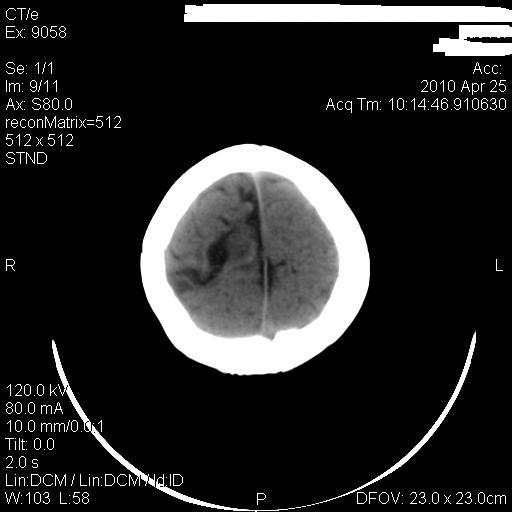

标题: PED3218:3岁女孩,曾有外伤史。未提供前片 [打印本页]

标题: PED3218:3岁女孩,曾有外伤史。未提供前片

发育略有障碍。欢迎大家发言。谢谢!

考虑右侧额顶叶脑软化灶并脑穿通畸形。

考虑:1)右侧额顶叶脑软化灶并脑穿通畸形。2)胼胝体发育不良。

支持考虑:1)右侧额顶叶脑软化灶并脑穿通畸形。2)胼胝体发育不良。

1)右侧额顶叶脑软化灶。2)胼胝体发育不良?

考虑右侧额顶叶软化灶并脑穿通畸形,胼胝体发育不全。

还有脑室周围白质软化症